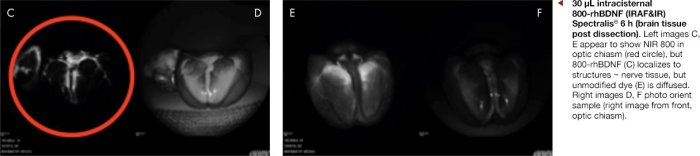

This study showed that when 800-rhBDNF is injected intracisternally in a single dose, midline at the base of the skull where the optic nerve originates, the NIR dye was localized to the optic nerve and transported to the optic nerve heads. Data were presented in a poster in collaboration with Absorption Systems (San Diego, CA) at Military Health System Research Symposium, August 2019. An excerpt from that poster is given below.